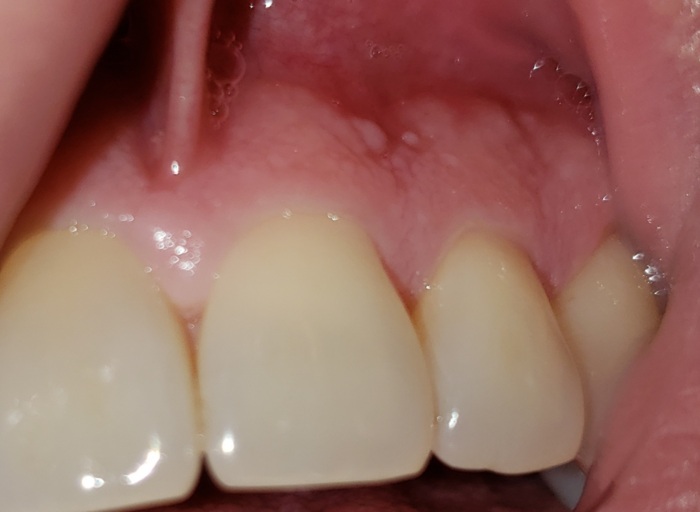

Please help, i'm so worried. I had a resin composite build up with two metal pins for my top front tooth after it broke off at the gums. Dentist asked if I had injured that tooth before because the nerve looked damaged. It was beautiful and matched my crown next to it. That was six days ago and since, it has turned almost black, along with the two lower front teeth below it which were filled in August when being fitted for a metal cast partial. The partial was not fitted properly and pushes against upper front teeth, moves around, shows gaps and my gums are irritated and taste like metal when removing it. (Getting new partial started in January). Just really concerned as this has never happened with my fillings or teeth before. I only drink water with one cup of coffee in the morning, don't smoke, drink or do drugs. Top picture is 6 days ago, bottom is this evening.

In the 20 years I have been in dentistry, I have never seen composite resin stain in the way it is pictured. If it is not extrinsic stain resulting from something you have eaten or drank, it could be a reaction of the metal pins and the resin used. The before picture you posted the teeth match beautifully. Either way, this is something that needs to be brought to the attention of your dentist immediately.